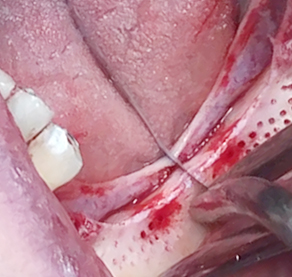

Implants/Bone Grafting

Partial edentulous clinical cases